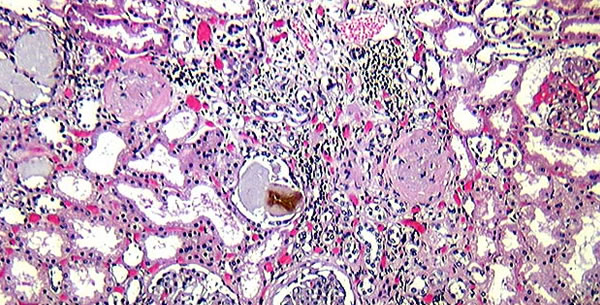

Na bubrezima je ovo posebno vidiljivo. Hiperkalcemija u krvi uzrokuje calcinuriu i kalcij koji uđe u glomerularni filtrat nerijetko u bubrežnim kanalićima se obori u kompleksima sa proteinima i ostacima ćelijskog raspada stvara kacijeve cilindre koji žačepljavaju put primarnom urinu stvarajući opasnost od uremije. Pored toga kalcij se ne taloži samo u kanalićima nego i u raspadnutim ćelijama kanalića uzrokujući još i upalu u intersticiju što pogoršava još više to stanje. Ove promjene jednim imenom označavamo kao nephrosis calcarea.